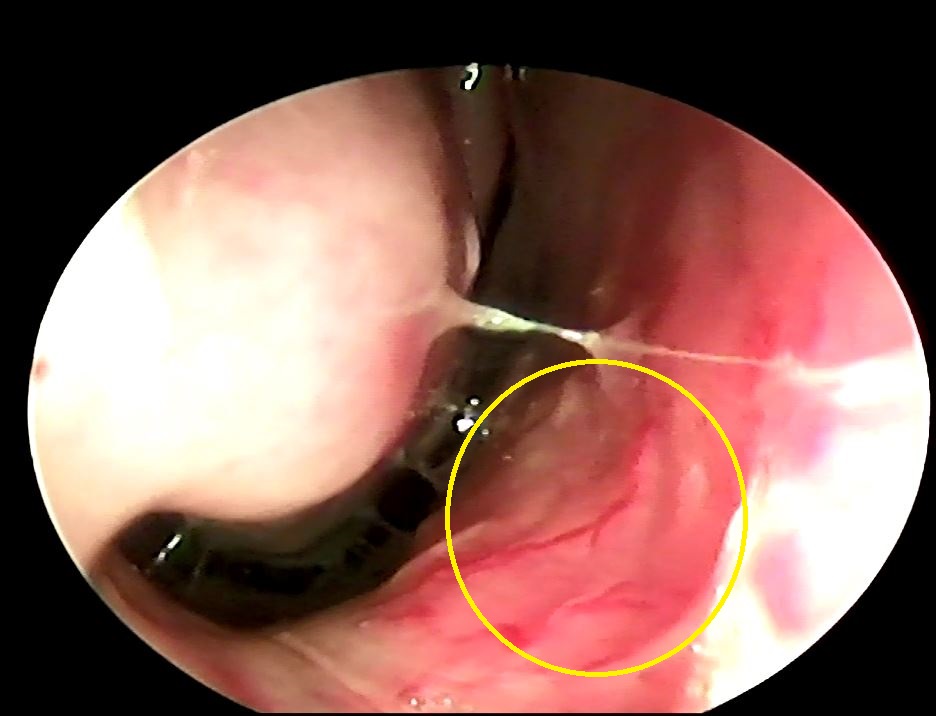

一般人遇到流鼻血的時候都會非常驚慌,其實我們越是驚慌血壓會越高有時候反而會流的越厲害,以前在醫學中心當住院醫師的時候,常常一個早上要拔很多鼻棉條 (鼻部手術的病人預計要出院),我都會先跟病人溝通之後會做什麼事情讓他先理解請他盡可能放鬆心情不要緊張,這個事前的預防動作讓我很少碰到拔完之後大出血的情形,所以遇到流鼻血的情況請先深呼吸坐下來把鼻子捏好,鼻腔前緣的鼻中隔血液循環豐沛(有五條血管支配)(內視鏡圖可以看到血管)因此是最容易流血的區塊,通常如果按壓正確幾分鐘左右應該就會止血,一般不建議去鼻腔內塞東西免得造成二次傷害,如果持續流血超過30分鐘請趕快至耳鼻喉科就診!!